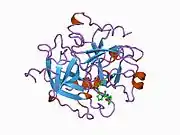

Structure

The molecular weight of prothrombin is approximately 72,000 Da. The catalytic domain is released from prothrombin fragment 1.2 to create the active enzyme thrombin, which has a molecular weight of 36,000 Da. Structurally, it is a member of the large PA clan of proteases.

Prothrombin is composed of four domains; an N-terminal Gla domain, two kringle domains and a C-terminal trypsin-like serine protease domain. Factor Xa with factor V as a cofactor leads to cleavage of the Gla and two Kringle domains (forming together a fragment called fragment 1.2) and leave thrombin, consisting solely of the serine protease domain.[17]

As is the case for all serine proteases, prothrombin is converted to active thrombin by proteolysis of an internal peptide bond, exposing a new N-terminal Ile-NH3. The historic model of activation of serine proteases involves insertion of this newly formed N-terminus of the heavy chain into the β-barrel promoting the correct conformation of the catalytic residues.[18] Contrary to crystal structures of active thrombin, hydrogen-deuterium exchange mass spectrometry studies indicate that this N-terminal Ile-NH3 does not become inserted into the β-barrel in the apo form of thrombin. However, binding of the active fragment of thrombomodulin appears to allosterically promote the active conformation of thrombin by inserting this N-terminal region.[19]